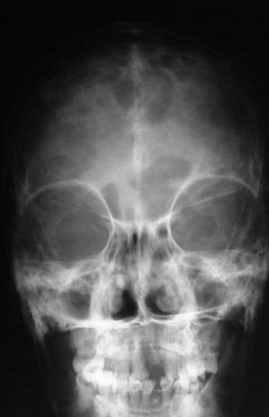

Уажаемые коллеги, представленные рентгенограмммы я показывал на нашем х-рей митинге - они были встречены с большим интересом.. Ну, ещё бы - я сам эту патологии встречал раза три за всю свою долгую жизнь:

После меня выступал с новыми находками для своей коллекции Эмануэл Лакью Тесема, хирург-ортопед из Эфиопии: Мне понравились его находки:

Кто шустрый - при какой патологии встречается так называемые "суставы Шарко"? Второе приобретение доктора Эмануэла мне понравилось своим романтическим названием: Candle bone - <кость-в-виде-оплывающей-свечи> : Просто редкая патология: